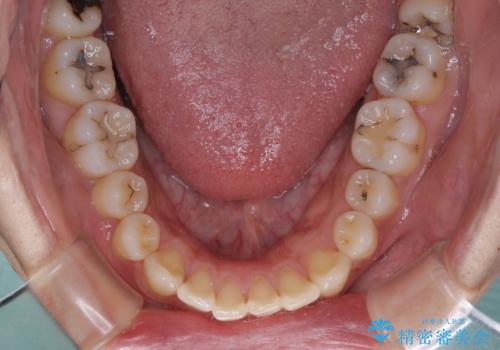

深い咬み合わせと前歯の隙間 ハーフリンガルによる矯正治療

- 30代男性

- 咬み合わせにより上顎正中に隙間ができているとのことで来院された患者様です。